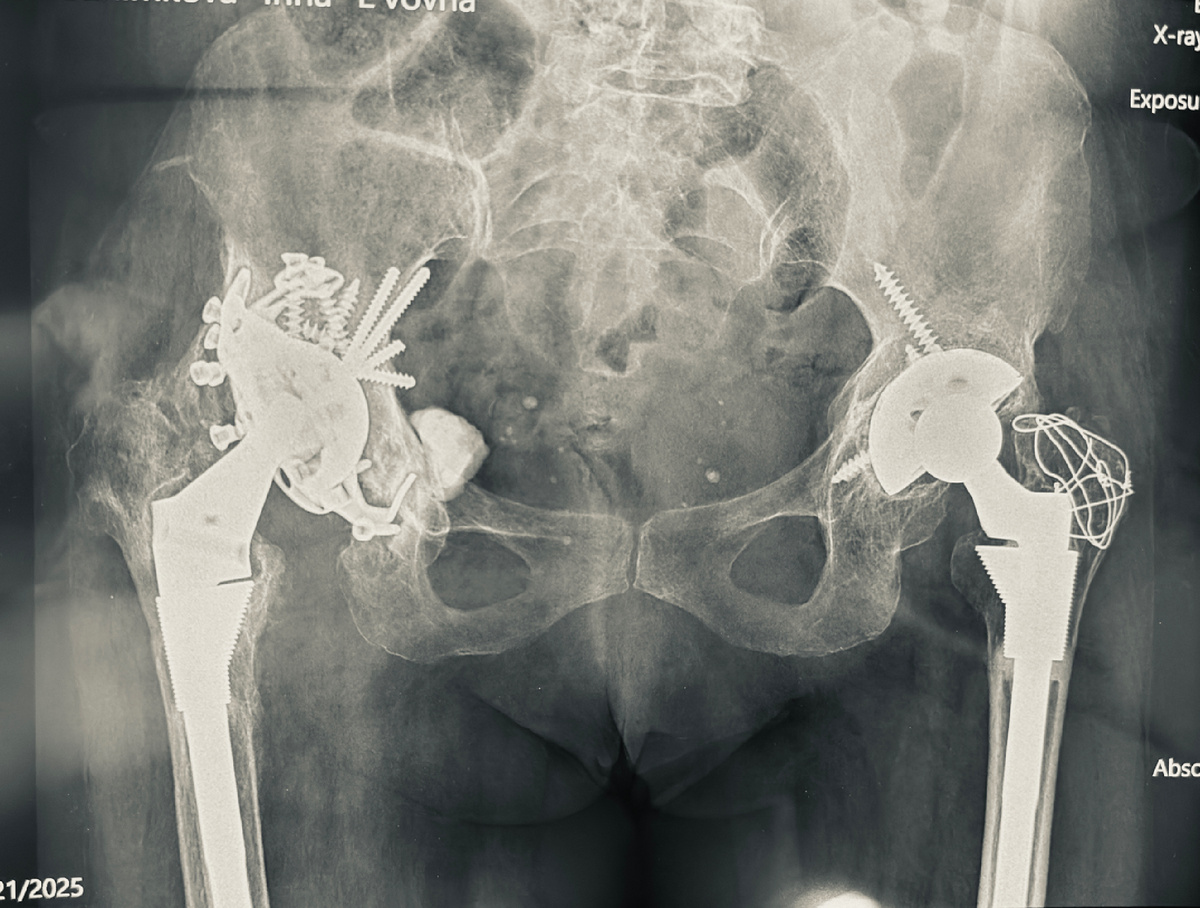

Пример. Женщина 65 лет с двусторонним врожденным вывихом головок бедренных костей. Оперирована в 30 лет профессором Мовшовичем в ЦИТО. Простейшие эндопротезы, одни из первых. Жизнь наладилась - боли ушли, походка выровнялась, семья, дети, работа.

Тот факт, что простые протезы, плюс исходно плохая ситуация с костями (дисплазия - недоразвитие суставов) послужили причиной довольно ранней нестабильности эндопротезов, как раз лет через 10. В 2002 году в Израиле оба эндопротеза последовательно заменили на ревизионные, получилось вот так:

Не комментирую ни выбор конструкций, ни положение. Важно другое: на этом человек нормально жил и ходил еще 23 года!!! Сейчас - только с тростью, но без этих операций уже давно была бы полная инвалидность - как минимум костыли, как максимум - коляска.

Сейчас развилась нестабильность конструкции, установленной справа. Что неудивительно - там исходно ситуация была хуже.

Что делать в такой ситуации? Удалять как минимум все, что установлено в вертлужную впадину таза, и, скорее всего, замещать индивидуальной конструкцией, напечатанной на 3D-принтере. Ножка, скорее всего, стабильна.